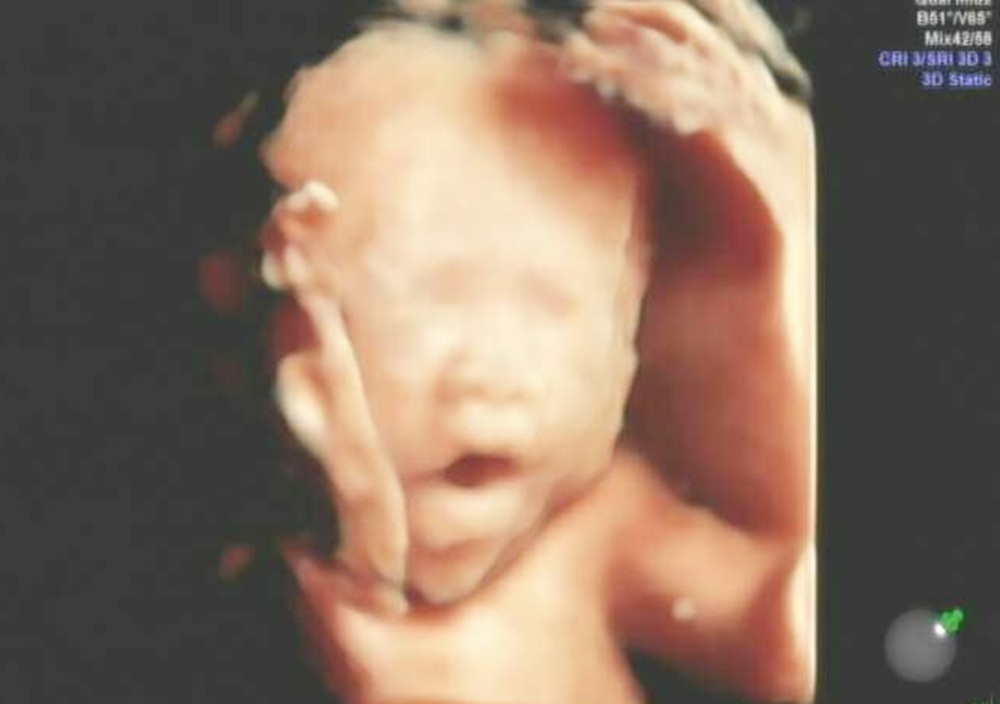

四维检查机器的原因

虽然很多人看到出生的孩子和四维很像,但仔细分辨看还是有很大差别的。即便是成人通过四维扫描拍出来的照片也不会太好看,何况是小婴儿。

小编想说四维的照片只是一个参考,无论美丑只要健康就好。所以妈妈也不要因为一张照片影响心情,等待宝宝出生之后自然就知道了。